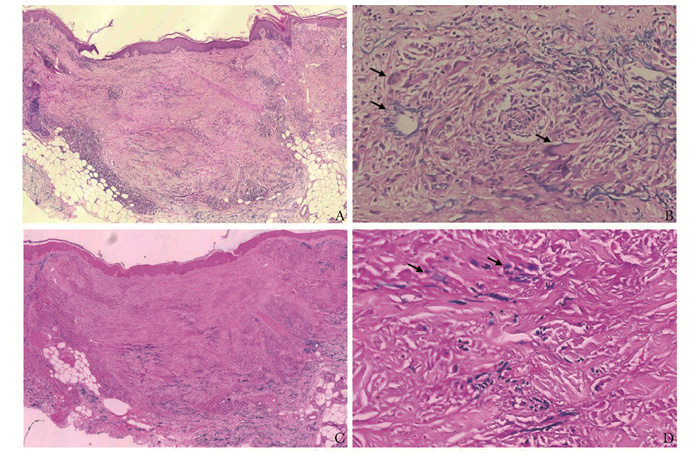

环状弹性纤维溶解性巨细胞肉芽肿一例

乔祖莎, 晋红中

2023, 2(2): 285-289. DOI: 10.12376/j.issn.2097-0501.2023.02.015